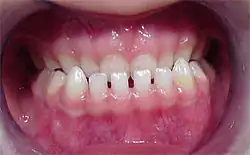

Un diastème (ou diastématie) (du grec διάστημα / diástêma, « intervalle ») est, en odontologie, un écartement entre deux dents normalement adjacentes. Il est plus fréquemment rencontré entre les deux incisives centrales de la mâchoire supérieure. Il peut être congénital ou acquis.

Diastème interincisif

Le diastème entre les incisives supérieures (diastème interincisif) est dû à la présence d'un frein labial (tendon qui attache les lèvres à la mâchoire) trop puissant et qui ne se rétracte pas suffisamment lorsque les dents poussent[1]. Il peut être dû aussi à une pulsion de la langue lors de la déglutition et/ou de l'articulation.